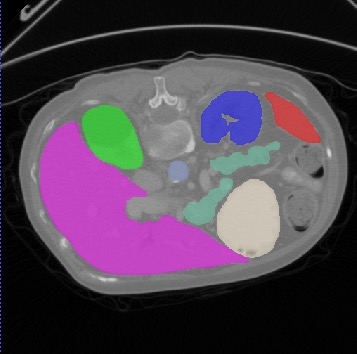

Transformers, the default model of choices in natural language processing, have drawn scant attention from the medical imaging community. Given the ability to exploit long-term dependencies, transformers are promising to help atypical convolutional neural networks (convnets) to overcome its inherent shortcomings of spatial inductive bias. However, most of recently proposed transformer-based segmentation approaches simply treated transformers as assisted modules to help encode global context into convolutional representations without investigating how to optimally combine self-attention (i.e., the core of transformers) with convolution. To address this issue, in this paper, we introduce nnFormer (i.e., Not-aNother transFormer), a powerful segmentation model with an interleaved architecture based on empirical combination of self-attention and convolution. In practice, nnFormer learns volumetric representations from 3D local volumes. Compared to the naive voxel-level self-attention implementation, such volume-based operations help to reduce the computational complexity by approximate 98% and 99.5% on Synapse and ACDC datasets, respectively. In comparison to prior-art network configurations, nnFormer achieves tremendous improvements over previous transformer-based methods on two commonly used datasets Synapse and ACDC. For instance, nnFormer outperforms Swin-UNet by over 7 percents on Synapse. Even when compared to nnUNet, currently the best performing fully-convolutional medical segmentation network, nnFormer still provides slightly better performance on Synapse and ACDC.